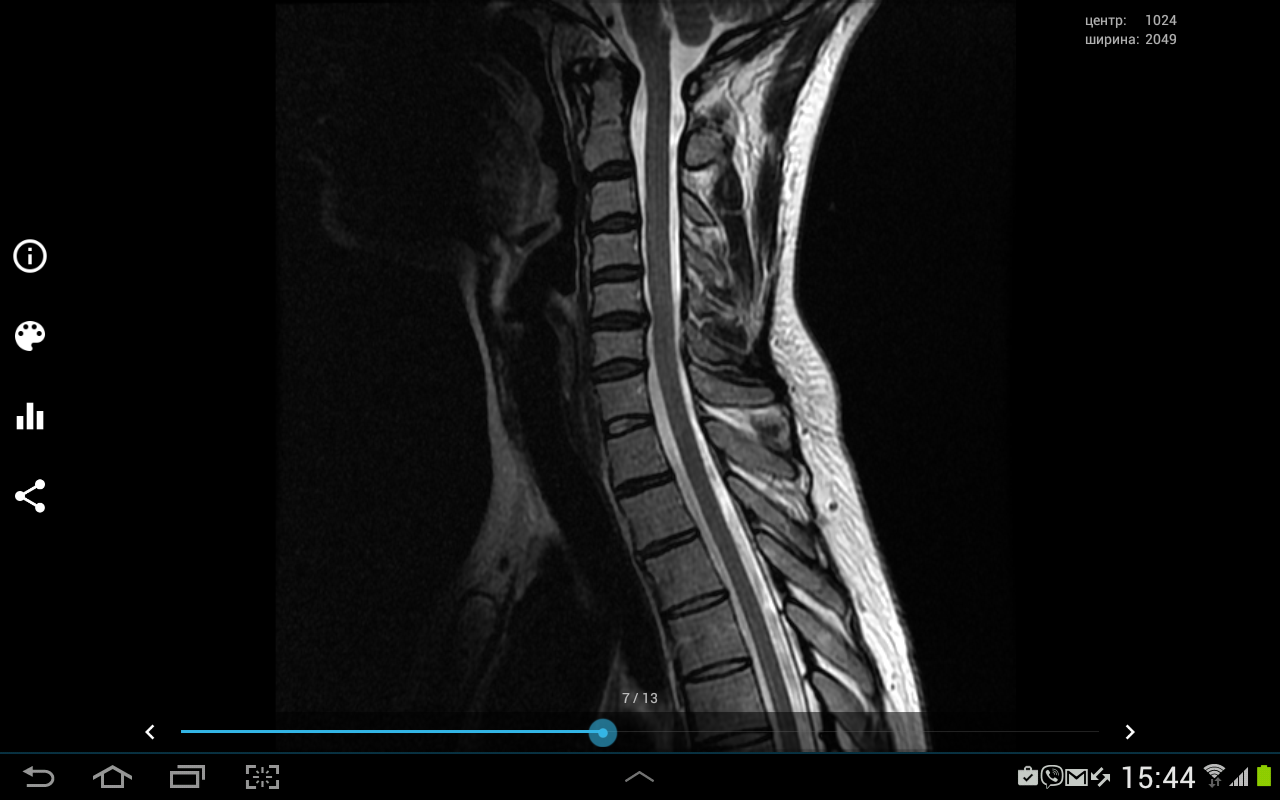

Здравствуйте подскажите пожалуйста надо делать операцию или нет? Наш нейрохирург говорит что надо, невролог говорит что не надо не знаю кого слушать, помогите. У меня ноющие боли в шее, переходящие на левую руку и под лопатку,иногда немеют кончики пальцев на руках, также есть иногда головные боли!?

Screenshot_2016-11-22-15-46-26.png

МРТ

Screenshot_2016-11-22-15-45-40.png

Screenshot_2016-11-22-15-44-57.png